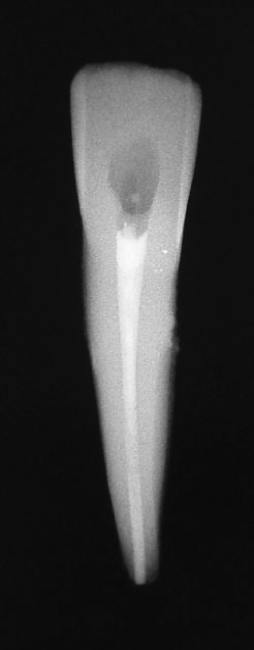

Another time when a post cannot be placed is when there is internal or external resorption. In the case shown in Figure 22, internal resorption occurred. Today it would be much easier to ascertain with CBCT. Here, the clinician filled the resorption with gutta-percha, and then above the gutta-percha, the mid-root coronal section was filled with composite. Because of how weakened the tooth was already, the clinician wanted to do whatever was possible to prevent it from weakening further. Figure 23 shows the postoperative radiograph, and Figure 24 shows the 2-year checkup. The only post that could be placed would have been a fiber post.

Fig 22. Internal resorption.

Figure 22